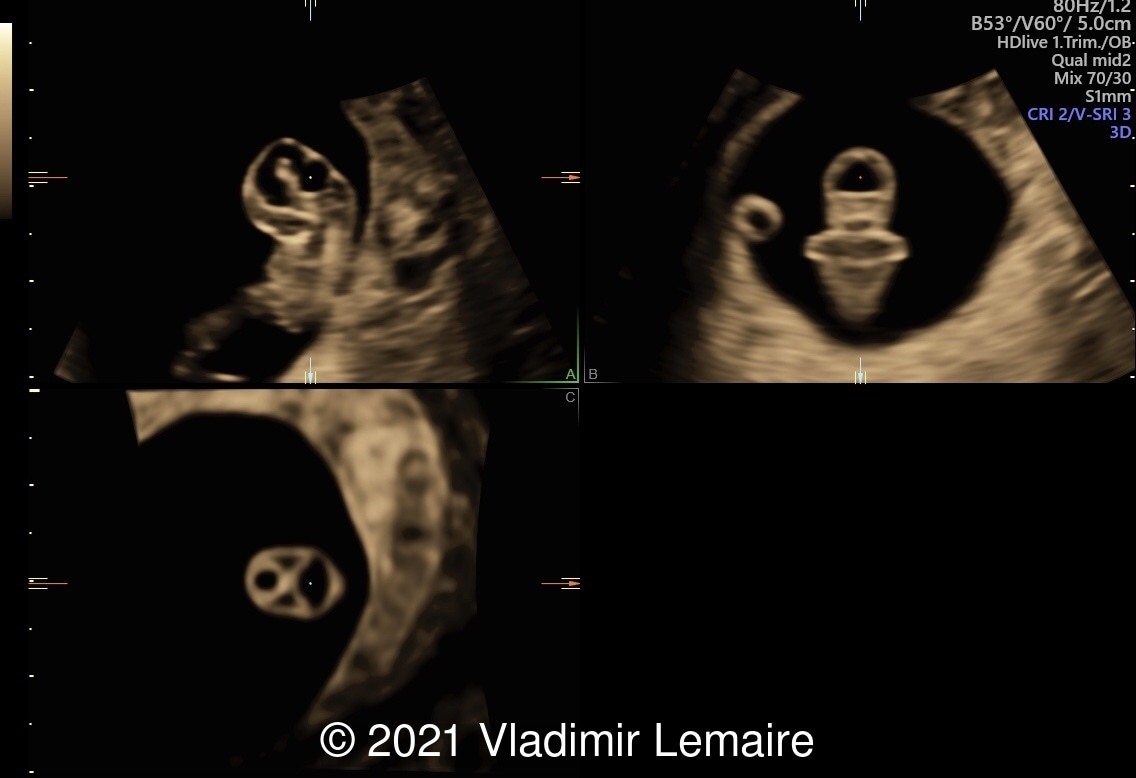

Three-dimensional ultrasound in multiplanar display of an embryo at 8weeks of gestation showing the brain vesicles.

Image 2 Three-dimensional ultrasound in multiplanar display of an embryo at 8weeks of gestation showing the brain vesicles.